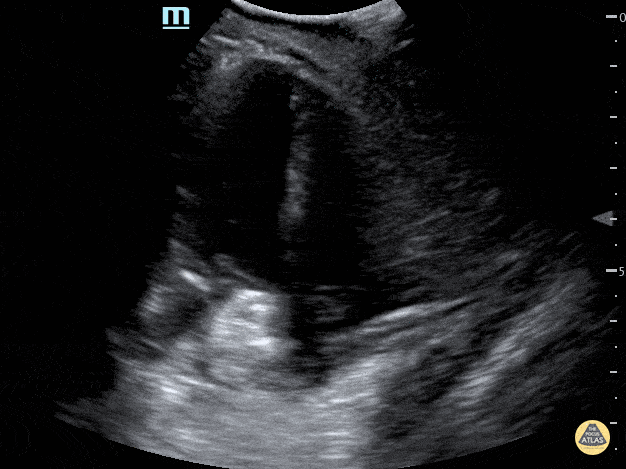

Peds-Cardiac - Apical 4 Chamber showing ASD closed with percutaneous device

Apical 4 chamber view showing an ASD occlusion device. Contributor: Peter Gutierrez, MD, FAAP, Emory University School of Medicine/Children's Healthcare of Atlanta, @pocuspete